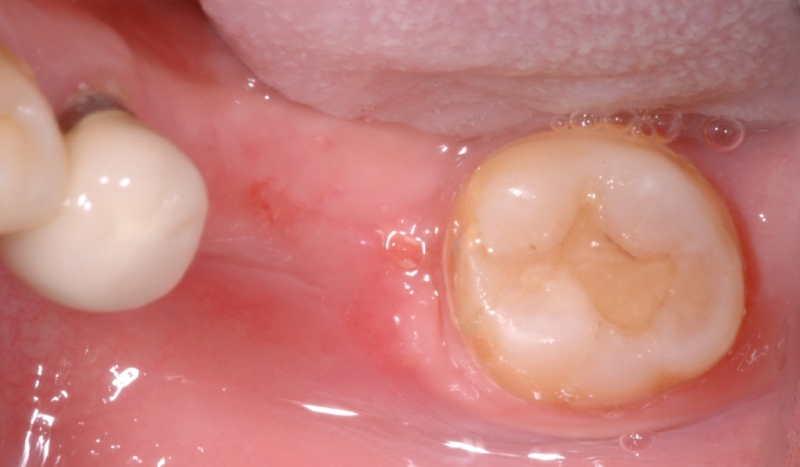

牙肉重建術案例

案例1

牙肉重建術前

牙肉重建術後